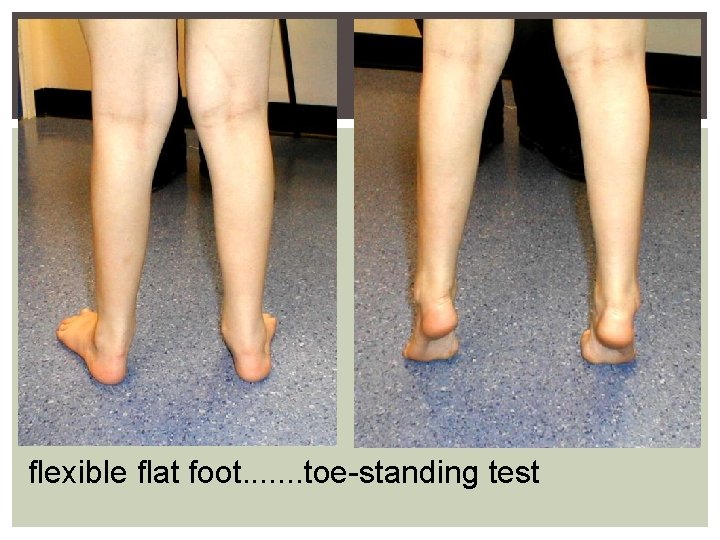

flexible flat foot. . . . toe-standing test